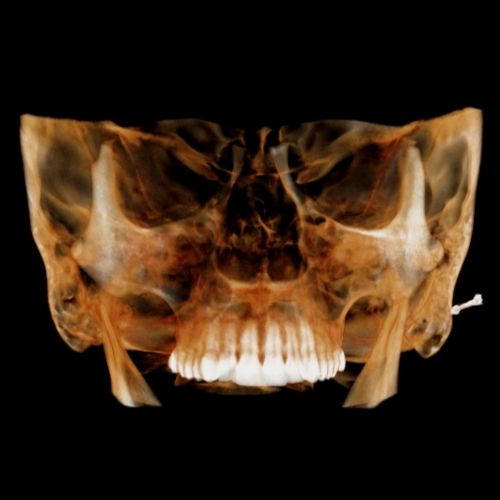

Slab and Cutting

Slab Feature allows the clinician to see inside structures while rotating the 3D image. Cut away structures to see exactly what is pertinent to your study.